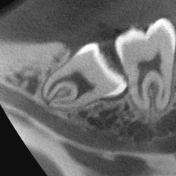

70μm(Voxel Size)高精細モード搭載

End、根尖、破析、分岐部病変など精細読影をサポートします。

CT撮影時、Free FOVで撮影に必要な領域を絞り込み、

的確に高解像度70μmの世界トップレベルのCT画像を再現します。-

根管END